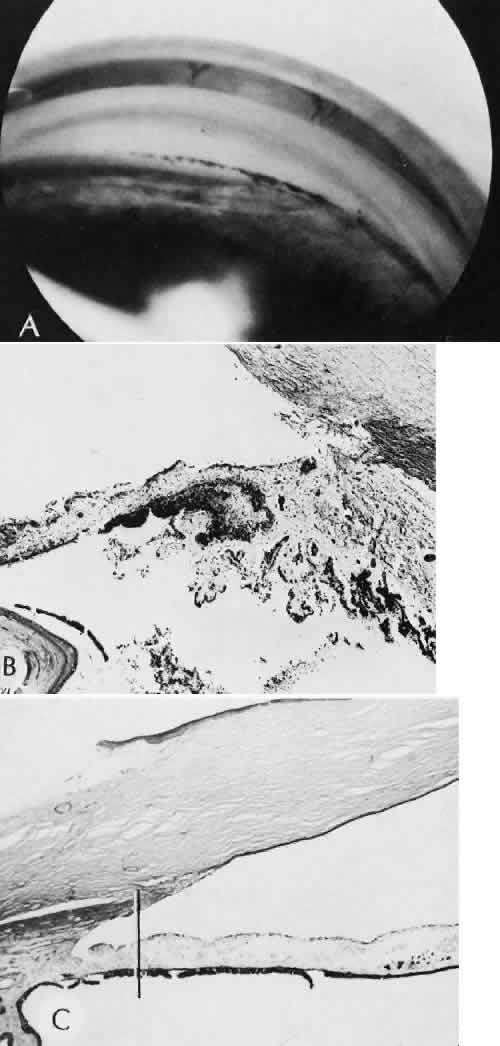

Infectious bacterial endophthalmitis (Figs. 39 and 40) usually presents early in the postoperative period.113,114 Pseudomonal and streptococcal organisms often cause rapid and total destruction of the eye. Organisms of especially low virulence, such as Staphylococcus epidermidis and Priopionibacterium acnes, may not present for months and may be misinterpreted as sterile endophthalmitis caused by a toxic reaction to intraocular lens materials or phacoanaphylactic endophthalmitis targeted to lens cortical remnants.115–117 Infectious endophthalmitispresenting months after surgery may be caused by a fungal infection or by bacteria of low virulence as pointed out above.

Fig. 39. A case of endophthalmitis following cataract extraction. A. An area of hypopyon inferiorly and a suture line secured with 8/0 silk sutures superiorly can be easily identified. The case is from the era of intracapsular cataract surgery, however, the risk of infection remains with all types of more recent procedures. B. In the histologic section an vitreous abscess in present. The lytic nature of bacterial infections has caused extensive gaping of the original limbal wound allowing herniation of inflamed intraocular tissue into the subconjunctival space. The retina is completely detached and necrotic. (Hematoxylin-eosin stain; × 5.)

Fig. 40. A case of suspected fungal endophthalmitis following cataract extraction. A. Well-demarcated, globular, opaque masses have developed over a period of weeks in the anterior chamber of a patient who had undergone cataract extraction. The lack of acute inflammatory activity, such as hypopyon formation, suggests a fungal infection. B. The anterior chamber reaction consists of a chronic inflammatory infiltrate characterized by multiple epithelioid histocytes, that is, a granulomatous inflammatory reaction consistent with fungal infection. (Hematoxylin-eosin stain; × 75.) C. A stain for fungus, however, does not reveal the presence of fungal forms. The material does stain with the silver stain, but the morphology is not that of a fungus. The features of the material suggest the inclusion of foreign material. (Gomori methenamine silver stain; × 75.) D. The material in the granulomatous inflammatory infiltrate appears to have a refractile nature when viewed at high magnification. (Hematoxylin-eosin stain; × 300.) E. The definitive test for foreign material is examination by polarized light. Under these conditions, the material can be identified as fibrous material consistent with cotton fibers. Cotton was apparently inadvertently introduced at the time of surgery. The inflammatory reaction is attempting to rid the eye of this foreign material, but the reaction is simultaneously destroying delicate ocular tissue. (Polarized hematoxylin-eosin stain; × 75.)